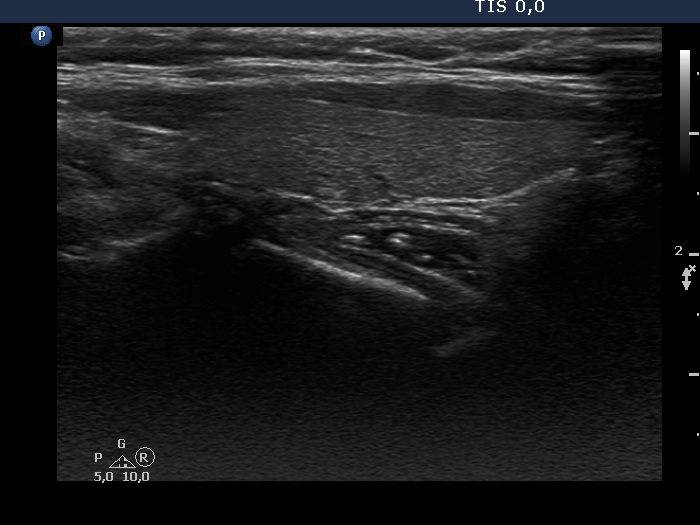

Consecutive patients with the final diagnosis of Hashimoto's thyroiditis - case 48 (1019) (ultrasonographic picture 5)

Left lobe, longitudinal view.